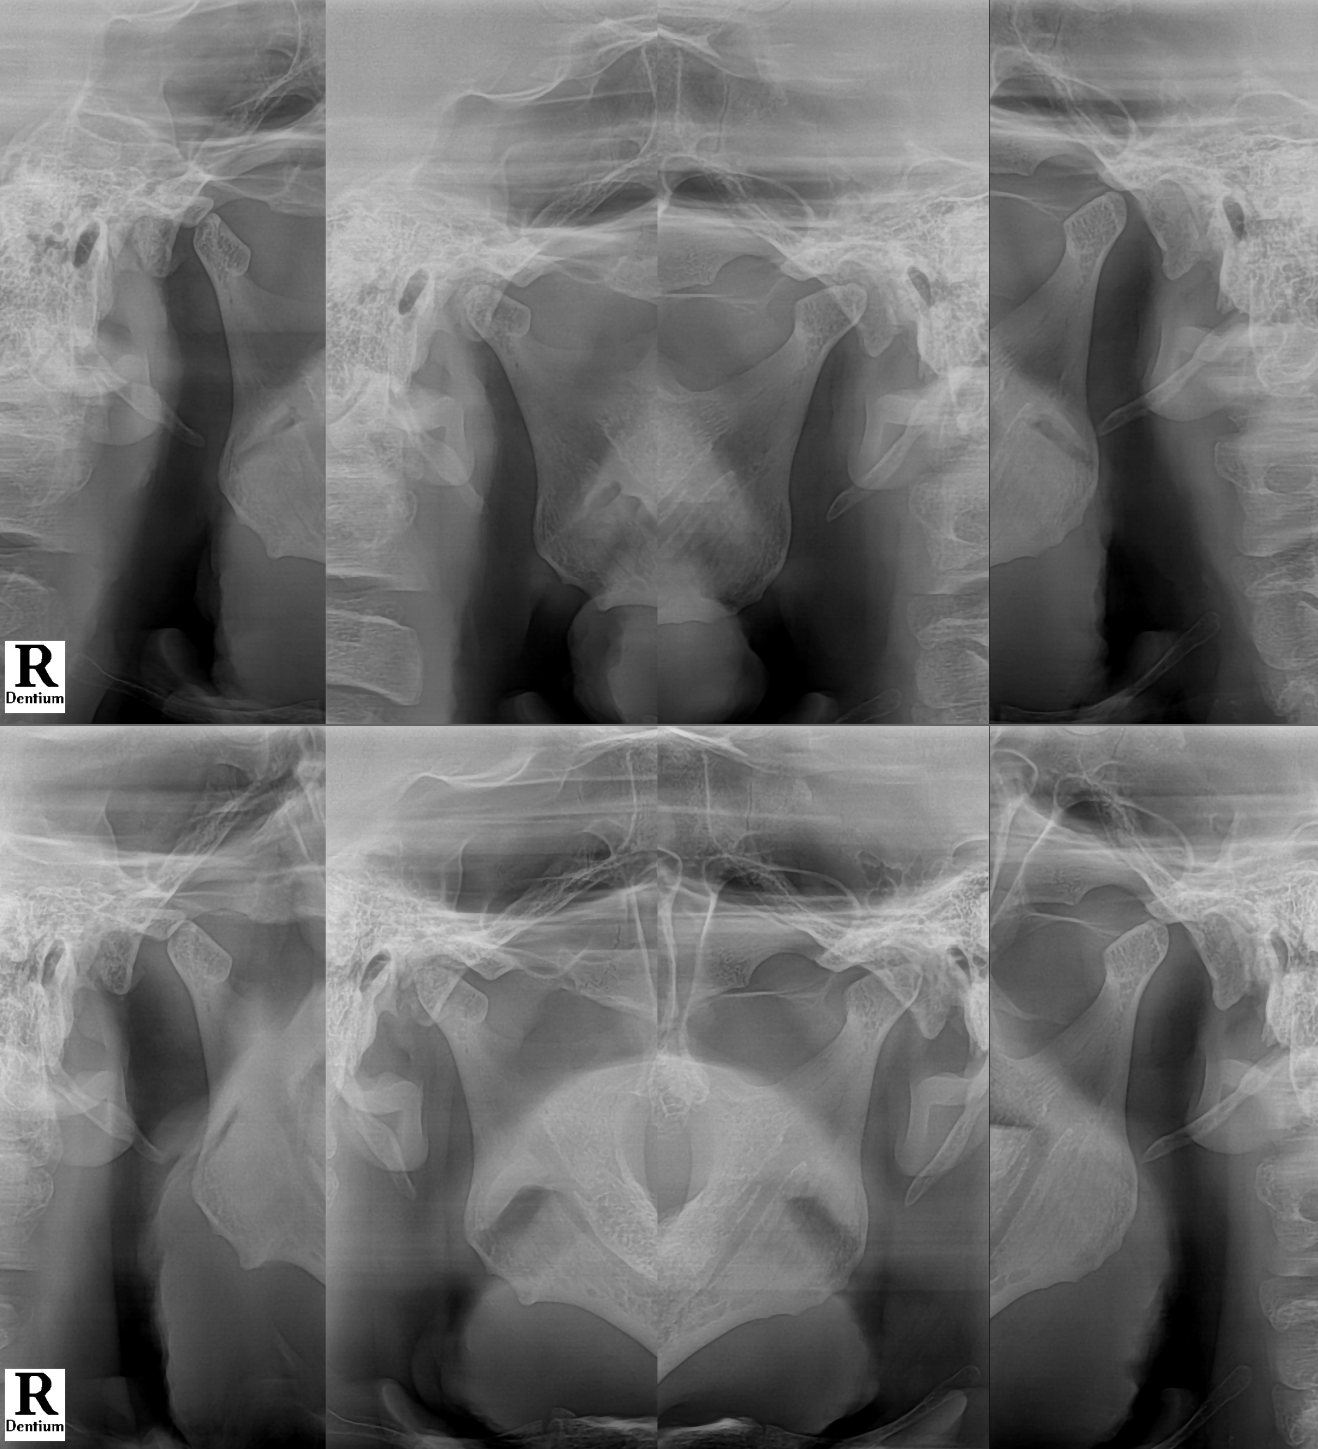

#CaseNo240473

왼쪽 턱관절이 아파요. 치악근이 원인? 완화기 필요?

이번 케이스에서는

주사 치료를 통해 근육의 과도한 힘을 줄이고

턱의 움직임을 안정화시키는 방향으로

총 5회의 외래 진료를 진행했습니다.